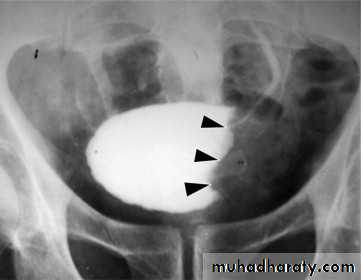

l.V.U. findings:

-Plain film may be useful in demonstrating calculi.-After contrast injection:

Acutely obstructed kidney shows a dense nephrogram (dense opacification of the renal parenchyma).excretion of contrast (opacification of the collecting system which may take many hours), then the level and degree of obstruction can be determined as dilated pelvi-caliceal system and ureter are followed down to the point of obstruction (point of hold up).